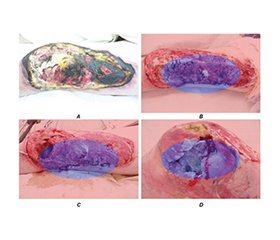

Актуальність. Тяжкі травматичні рани, особливо у військових умовах, часто ускладнюються розвитком хронічного, нейропатичного та фантомного болю. Раннє прогнозування больових синдромів залишається клінічною проблемою. Використання технологій штучного інтелекту (ШІ) відкриває нові можливості для інтеграції аналізу фотографій ран, мікробіологічних знахідок і даних щодо впливу медикаментів у прогностичні моделі. Мета: оцінити предиктори розвитку хронічного та нейропатичного болю після тяжких ран і перевірити точність платформи штучного інтелекту в прогнозуванні больових синдромів у військових. Матеріали та методи. Проспективне одноцентрове дослідження включало 311 військовослужбовців України з тяжкими ушкодженнями кінцівок (139 ампутацій). Збирали клінічні й демографічні дані, проводили мікробіологічні дослідження, аналізували серійні фото ран. У платформі використано штучний інтелект для сегментації ран, оцінки інфекції та прогнозування ризику розвитку хронічного, нейропатичного й фантомного болю. Результати аналізували через 3 і 6 місяців за шкалою NRS та опитувальником DN4. Результати. Через 6 місяців хронічний біль виявили у 42 % пацієнтів з ампутаціями, нейропатичний — у 29 %, фантомний — у 24 %. Незалежними предикторами були: інфекція рани (OR 2,1; 95% ДІ 1,4–3,2), затримка загоєння > 8 тижнів (OR 2,7; 95% ДІ 1,8–4,0), високий початковий рівень болю (NRS ≥ 7) (OR 1,9; 95% ДІ 1,2–3,0) і призначення нейротоксичних антибіотиків (OR 1,8; 95% ДІ 1,1–2,9). Платформа показала чутливість 78 %, специфічність 74 % та AUC 0,81. Висновки. Інфекція, затримка загоєння і прийом нейротоксичних препаратів є ключовими факторами ризику розвитку хронічного й нейропатичного болю після тяжких ран. Використання ШІ-платформи забезпечує клінічно значуще прогнозування ризику й може поліпшити персоналізоване лікування та реабілітацію військових.

Background. Severe traumatic wounds, particularly in military settings, are frequently complicated by chronic, neuropathic, and phantom limb pain. Early prediction of pain trajectories remains a clinical challenge. Advances in artificial intelligence (AI) enable integration of wound imaging, microbiology, and pharmacological data into predictive models. We developed and tested an AI-driven platform for the prediction of chronic and neuropathic pain after severe wounds. Materials and methods. A prospective observational study of 311 Ukrainian military patients with severe limb injuries (including 139 amputees) was conducted in 2022–2025. Clinical, demographic, and microbiological data were collected alongside serial wound photographs. The platform processed wound images to assess healing dynamics, identify infection-related risk, and compute the probability of chronic, neuropathic, and phantom pain. Pain outcomes were assessed at 3 and 6 months using the Numeric Rating Scale (NRS) and the DN4 questionnaire. Results. At 6 months, chronic pain was present in 42 % of patients, neuropathic pain in 29 %, and phantom pain in 24 % of amputees. Independent predictors of neuropathic pain included wound infection (odds ratio (OR) 2.1, 95% confidence interval (CI) 1.4–3.2), delayed wound healing (> 8 weeks) (OR 2.7, 95% CI 1.8–4.0), high baseline pain intensity (NRS ≥ 7) (OR 1.9, 95% CI 1.2–3.0), and exposure to neurotoxic antibiotics (OR 1.8, 95% CI 1.1–2.9). The platform achieved a sensitivity of 78 %, specificity of 74 %, and AUC of 0.81. Conclusions. Infection, delayed healing, and neurotoxic drug exposure are major predictors of chronic and neuropathic pain after severe wounds. The AI platform provides accurate, clinically relevant risk prediction and may support personalized pain prevention and rehabilitation in military trauma care.